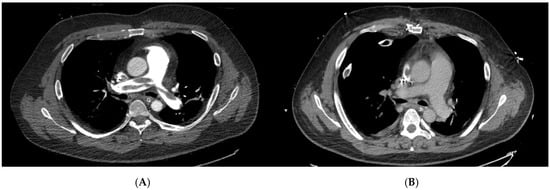

| Localization of PE via CTPA | ||||

| Bilateral central | 79 | 40 | 39 | 0.790 |

| Bilateral segmental | 1 | 1 | 0 | 0.999 |

| Right sided central | 3 | 2 | 1 | 0.5595 |

| Left sided central | 1 | 0 | 1 | 0.999 |

| Left sided segmental | 1 | 0 | 1 | 0.999 |

| Peripheral | 1 | 1 | 0 | 0.999 |

| not specified | 10 | 4 | 6 | 0.506 |